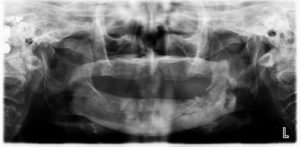

Osteoradionecrosis is defined as “necrosis of bone due to obstruction of its blood supply.” It is the late effect of radiation therapy which results in irreversible tissue death and clinically observed as bony exposure for more than 3 months duration. Mandible is mostly affected and most often body of the mandible more than 60 Gy exposure. Additional clinical consequences of radiation include taste loss or altered taste sensation, changes to the periodontium and trismus

The diagnosis of osteoradionecrosis is based on a history of radiation and clinical signs of severely painful, nonhealing exposed bone in the treatment area. Fistulae, sequestra, and pathologic fracture are other complications seen with osteoradionecrosis